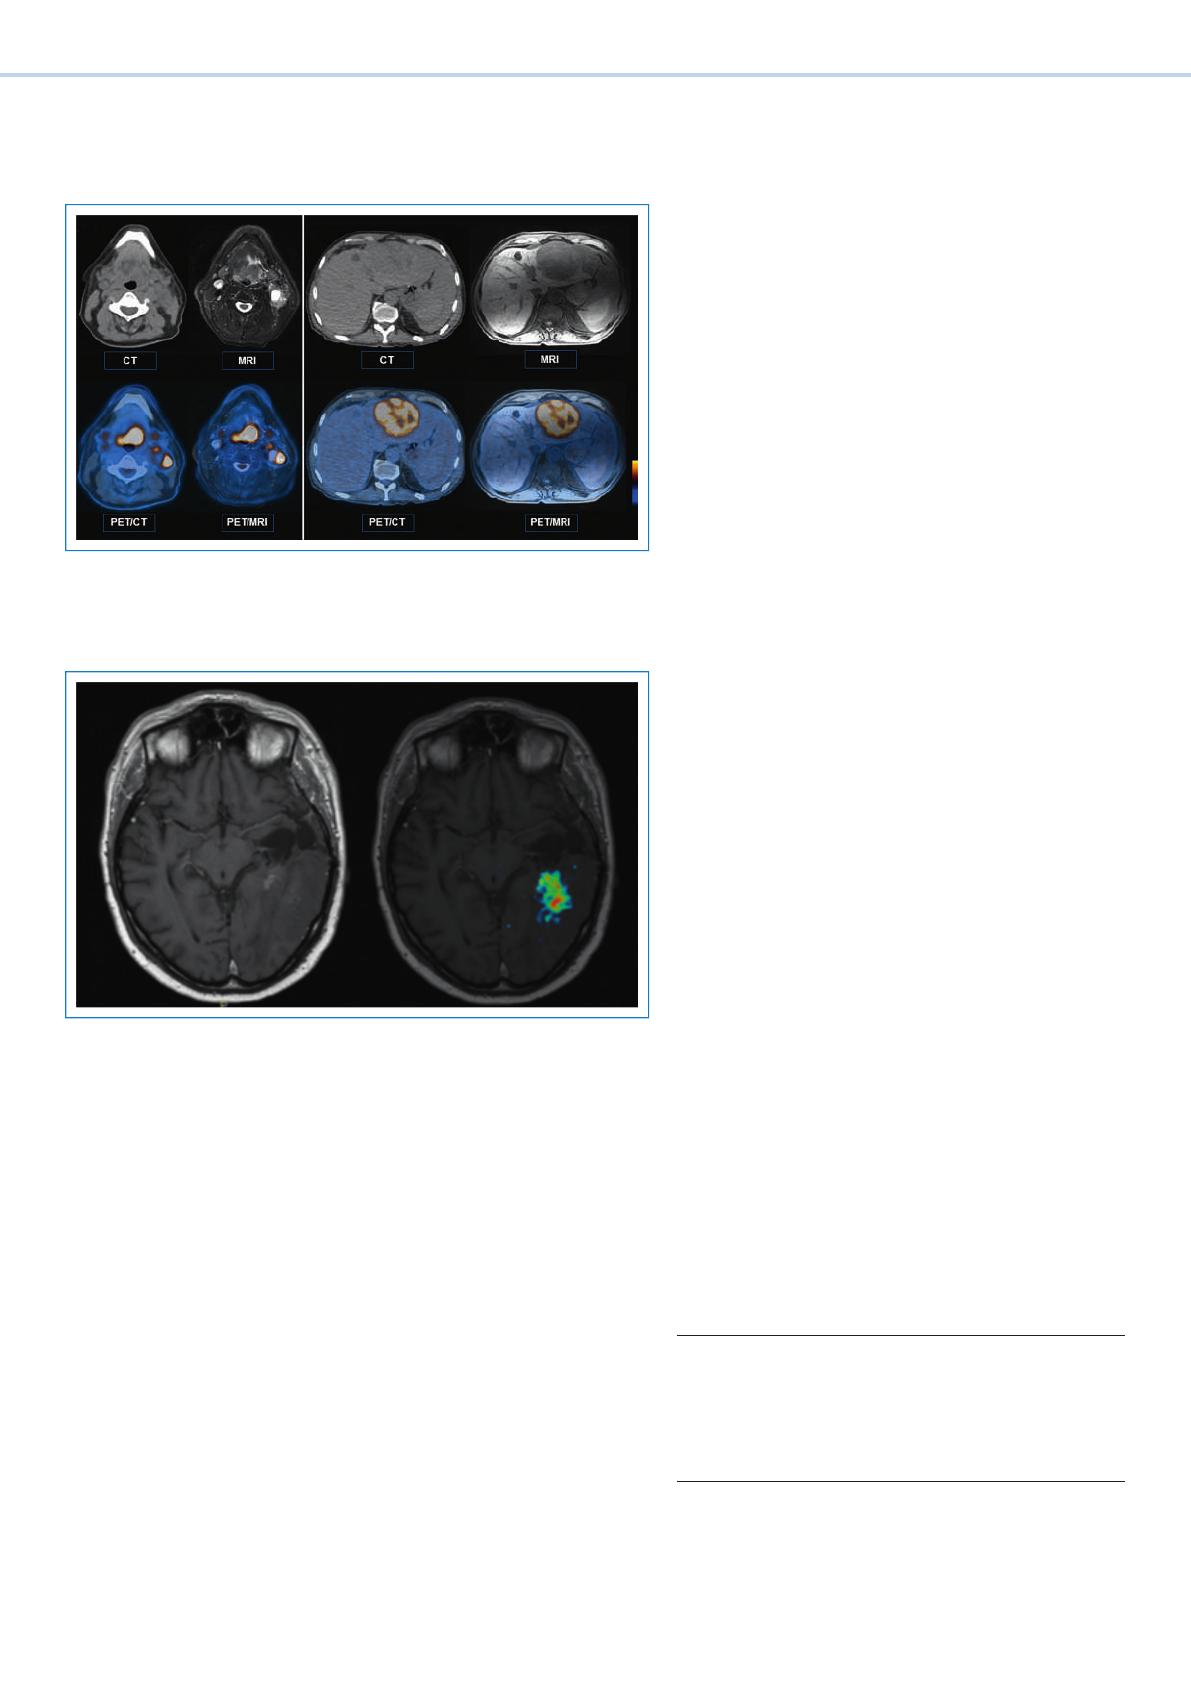

TEP/IRM: l’imagerie hybride de l’avenir

Compte du succès que connaît l’utilisation clinique des

appareils de TEP/TDM et des grands progrès réalisés

dans le développement de détecteurs TEP, des systèmes

TEP/IRM sont depuis peu évalués dans plusieurs grandes

cliniques universitaires. L’ unité d’imagerie médicale de

l’Hôpital universitaire de Zurich utilise depuis l’au-

tomne 2010 un système de TEP/TDM-IRM, qui allie la

TEP/TDM et l’IRM grâce à une table de transfert spécia-

lement développée. L’ acquisition séquentielle des don-

nées TEP, TDM et IRM et la fusion informatique des

images qui s’en suit permettent de comparer directe-

ment les images TEP/IRM avec les images TEP/TDM cor-

respondantes.

Par rapport aux images TDM, les images IRM présentent

un bien meilleur contraste des tissus mous, ce qui est par-

ticulièrement utile lors de l’exploration du cerveau et du

foie. En plus de l’anatomie macroscopique, l’IRM offre